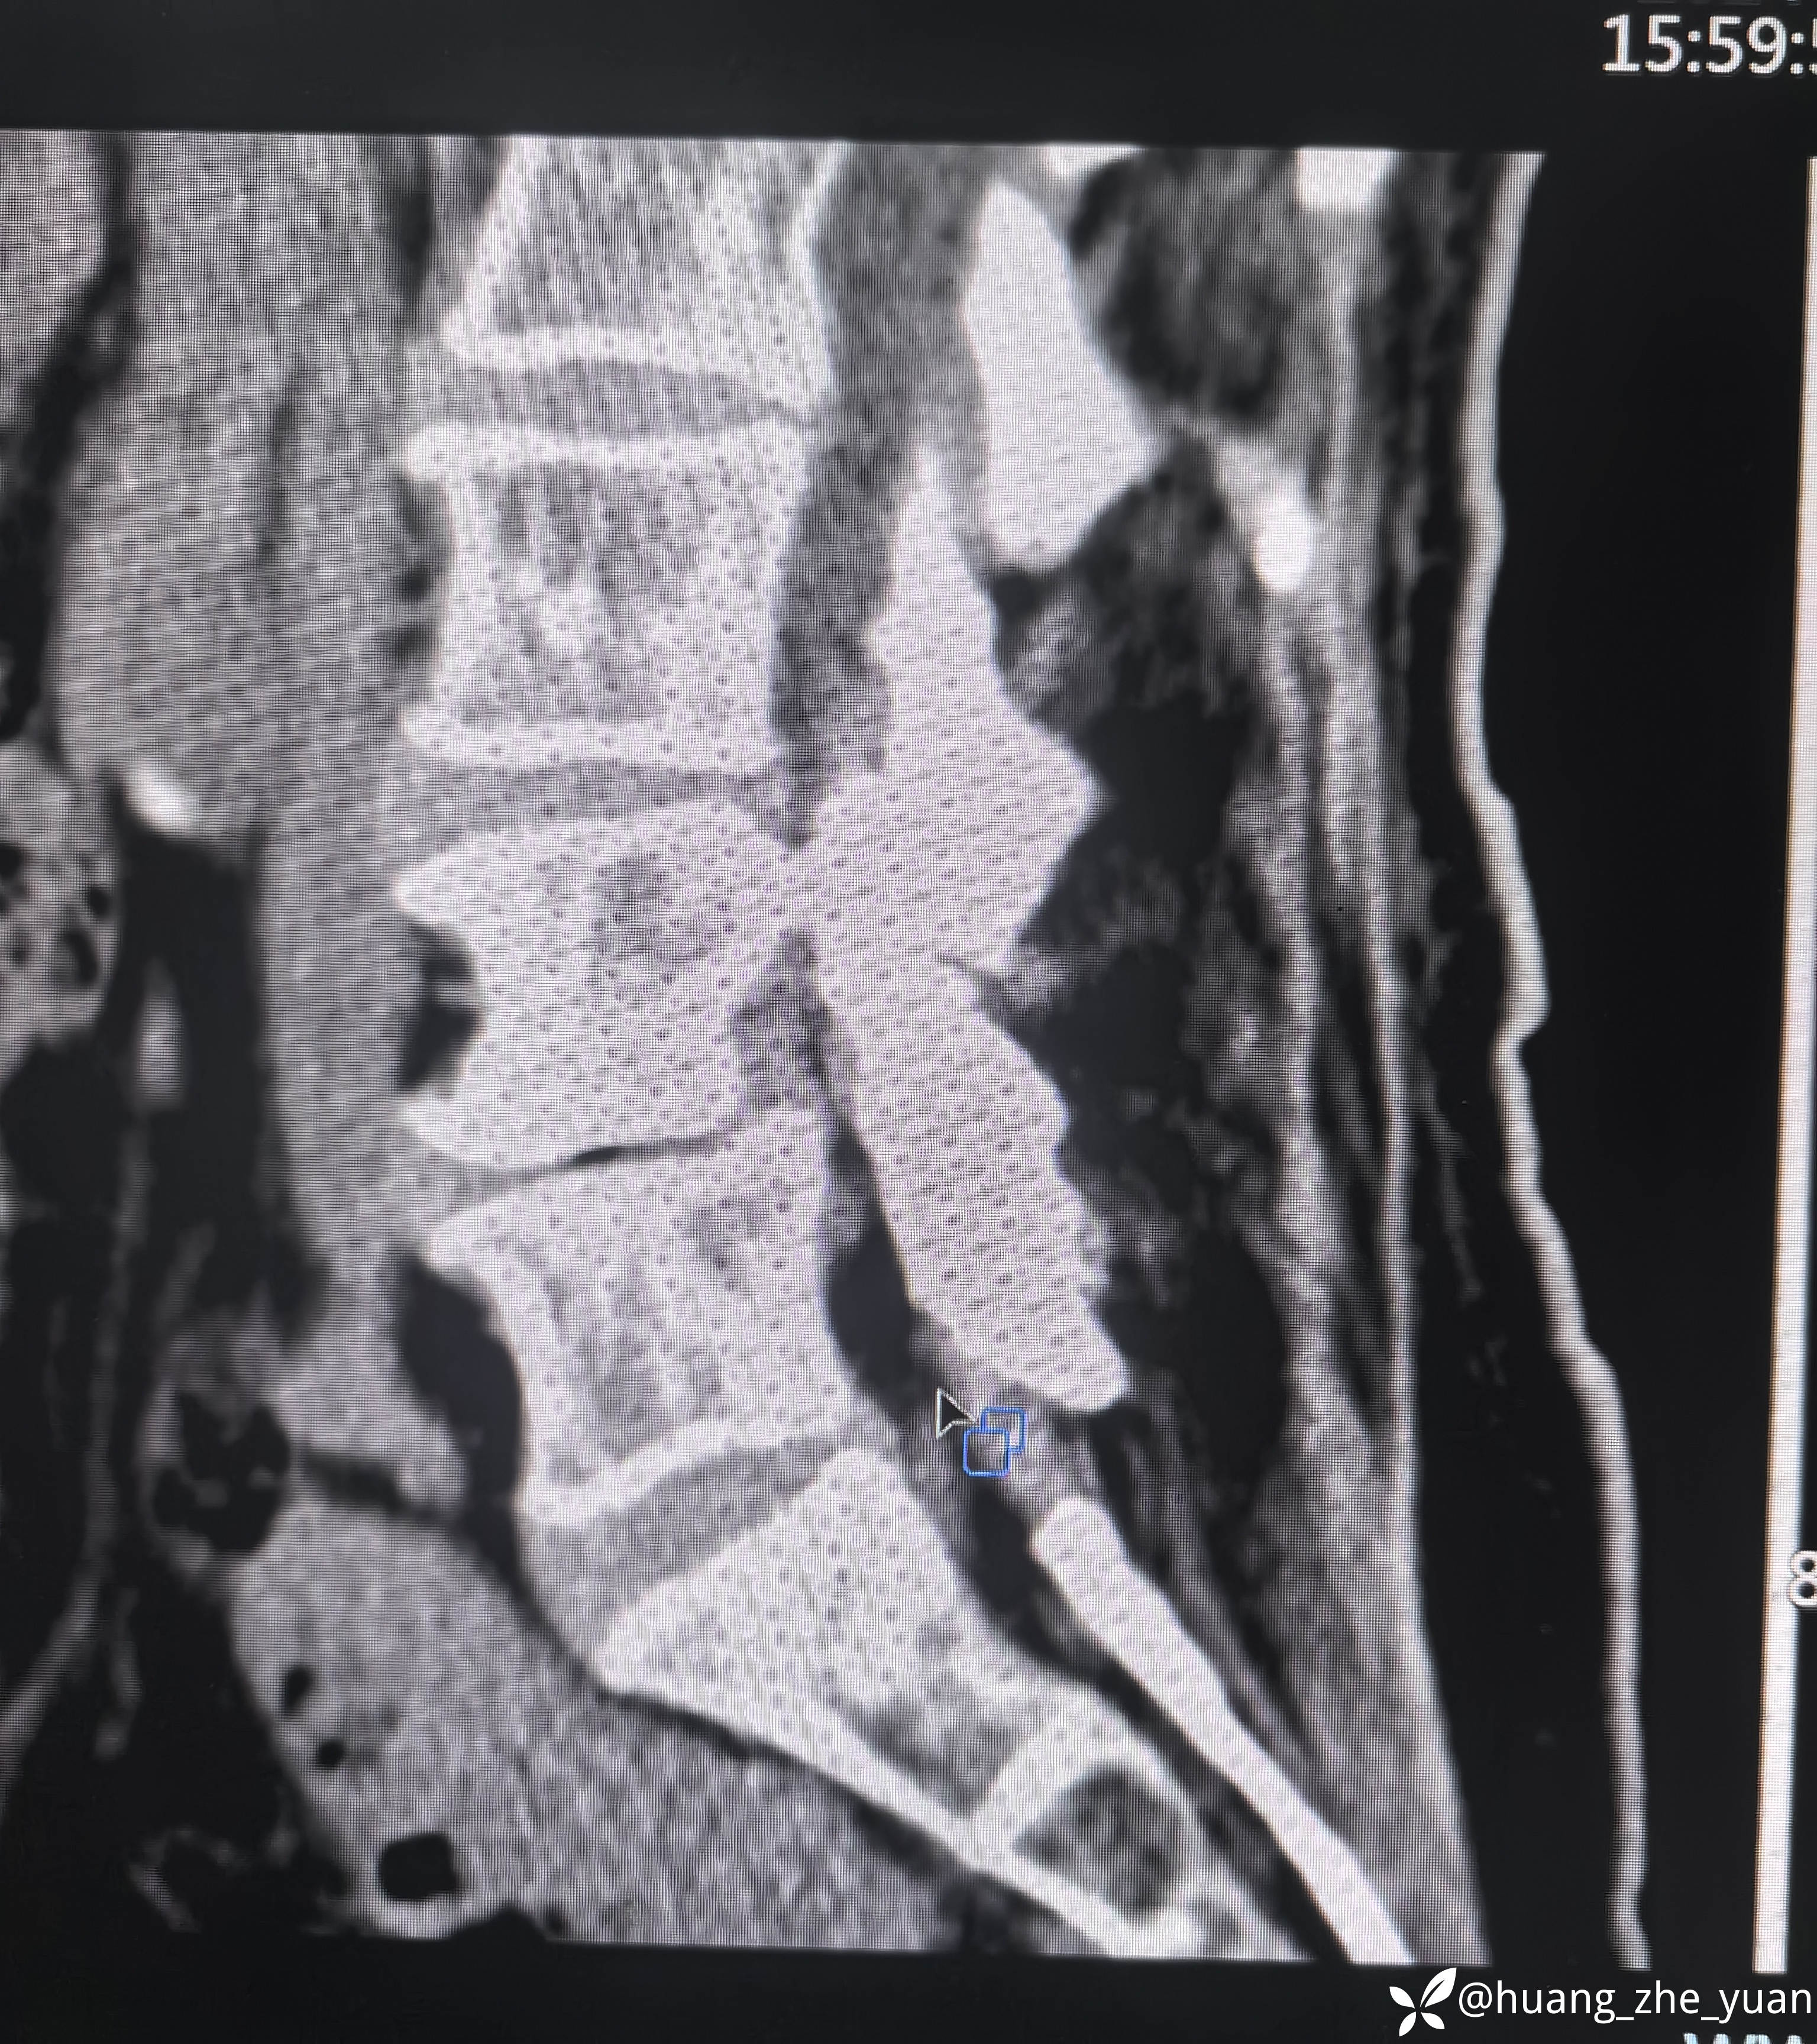

70岁女性,反复右下肢放射痛八个月。合并症:糖尿病,胰岛素泵控制。

1、有哪些手术入路方式?

2、减压范围?